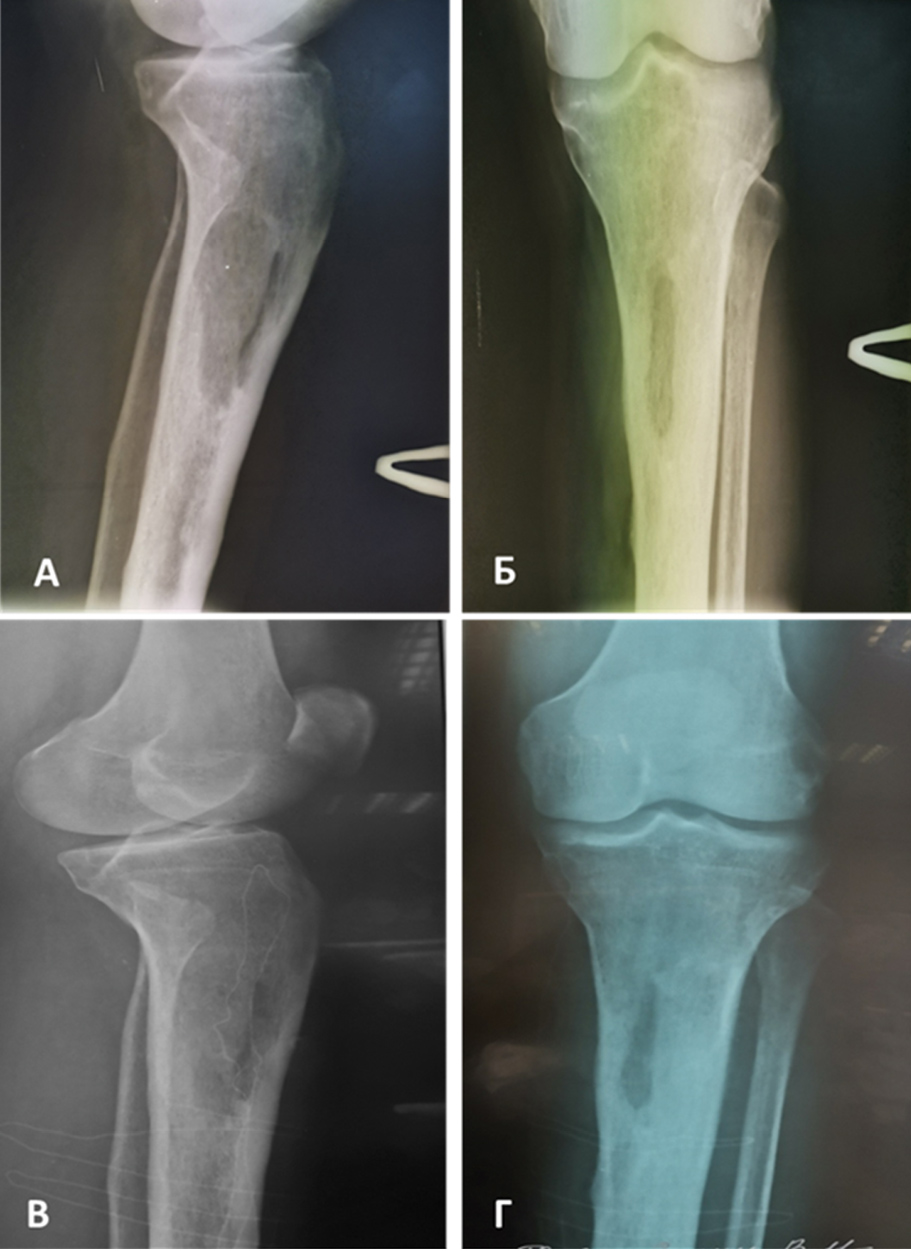

У всех пациентов было выполнено вскрытие костной полости, после ее обработки полость заполняли тромбогелем, изготовленным интраоперационно. Послеоперационный период протекал без осложнений. Пациенты были выписаны в удовлетворительном состоянии (рисунок 4). Максимальный период наблюдения составил 1,5 года. В представленных случаях рецидива остеомиелита выявлено не было.

Рисунок 4. Пациент, муж., 60 лет. Хронический посттравматический остеомиелит верхней трети левой большеберцовой кости, свищевая форма. Сопутствующие заболевания: Гипертоническая болезнь II ст., риск 3. Ожирение I ст. по ВОЗ (ИМТ 30 кг/кв.м). Выполнена фистулсеквестрнекрэктомия верхней трети левой большеберцовой кости с последующей хирургической обработкой, замещением костной полости кости тромбогелем. А–Б) Рентгеновские снимки в двух проекциях до начала лечения. В–Г) Рентгеновские снимки в двух проекциях через 2,5 месяца – положительная динамика. / Figure 4. Patient, male, 60 years old. Chronic post-traumatic osteomyelitis of the upper third of the left tibia, fistulous form. Concomitant diseases: Hypertension II stage, Risk 3. Obesity grade 1 according to WHO (BMI 30 kg / sq.m). Fistula-sequester-necrectomy of the upper third of the left tibia was performed, followed by surgical treatment, replacement of the bone cavity with platelet gel. A-B) X-rays in two projections before the start of treatment. C-D) X-rays in two projections after 2.5 months – positive dynamics.